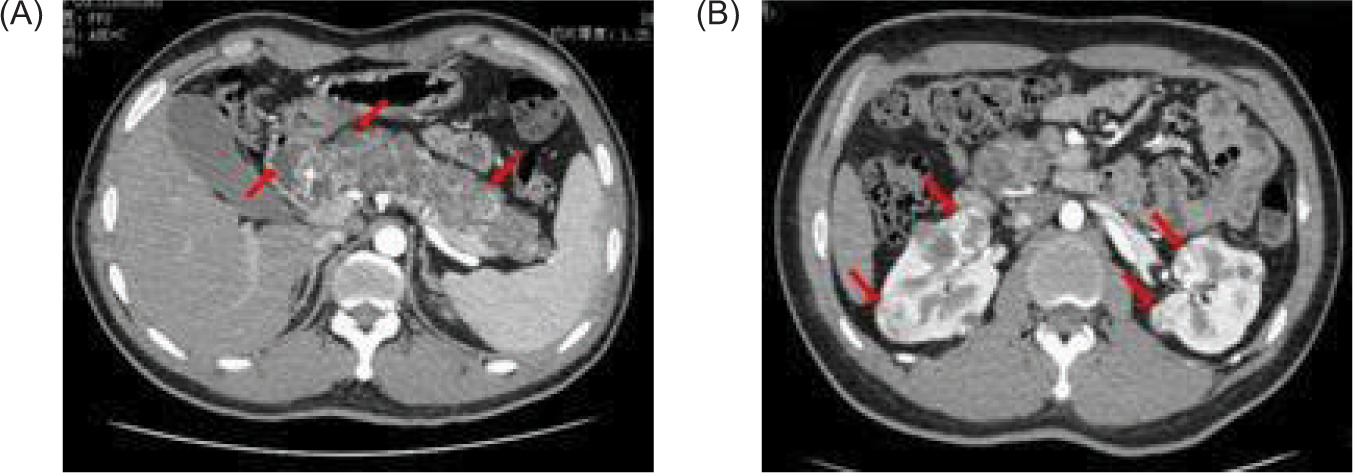

An abdominal CT on January 16, 2021 revealed renal and pancreatic masses, and an enhanced abdominal CT scan on January 18, 2021 showed multiple pancreatic cysts/cystadenomas and multiple kidney cancers in both kidneys and a small cyst in the left kidney (Figure 2). A cranial magnetic resonance imaging (MRI) done on January 29, 2021 revealed a possible mass in the right temporal bone jugular foramen, with a cross-sectional area of approximately 12×18 mm (Figure 3). The patient refused further examination of the brain and abdomen for personal reasons and denied any family history of VHL syndrome. He was diagnosed with DM and treated with tablet voglibose, 0.2 mg, three times daily (tds), and injection glargine insulin, 12 units once daily (OD). Despite the treatment, he continued to suffer from progressive weight loss over the next 6 months, losing an additional 7 kg.

Figure 2: Contrast-enhanced CAT (CT) scan of the abdomen shows (A) multiple low-density nodules in the pancreas (red arrow); (B) low-density nodules in the left kidney, and multiple nodules of different sizes in both kidneys, which were heterogeneous enhancement (red arrow).